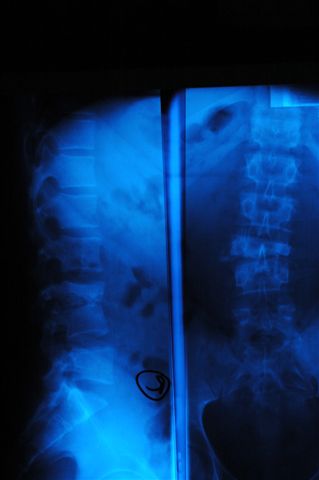

[Ortho] туберкулёзный спондилит

Обратился мужчина 40 лет с постоянными болями в поясничном отделе позвоночника, не купирующиеся аналгетиками, противовоспалительными препаратами

Соматически здоров, неврологического дефицита в конечностях, нарушений функции тазовых органов нет.

СОЭ - 4 , С-  реактивный белок -1